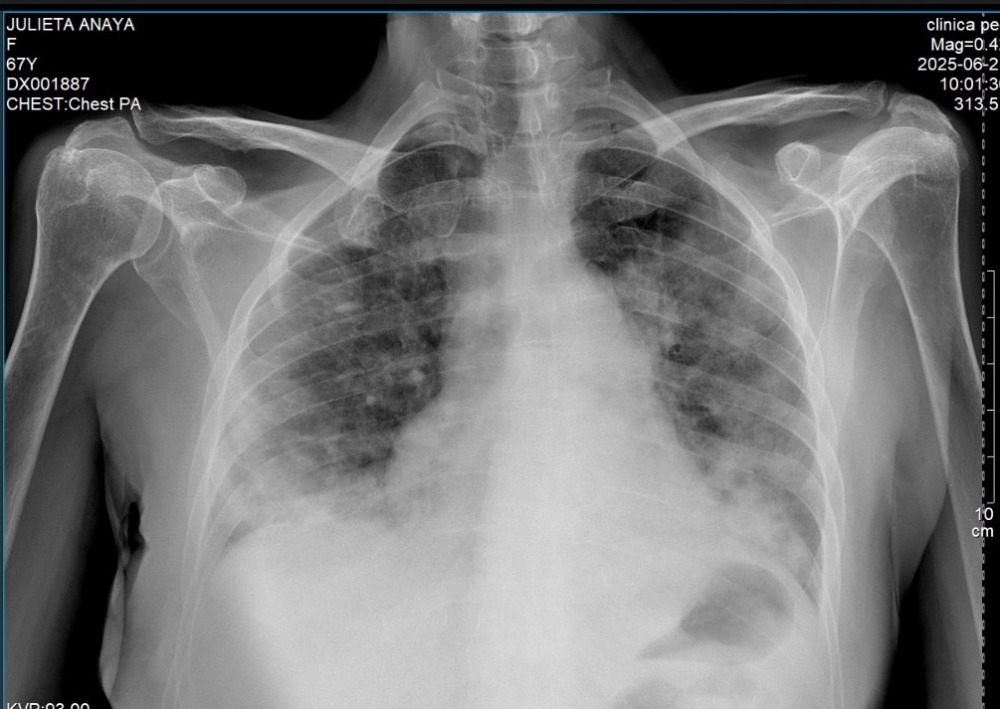

Our beloved mom, Julieta, was just diagnosed with pneumonia. For over two weeks, we believed she was fighting off influenza based on an initial medical opinion—enduring constant high fever, intense body pain, and serious difficulty breathing. She followed the treatment she was prescribed, but her condition didn’t improve. When we spoke with her during those days, it was clear how much she was suffering.

After seeing no signs of recovery, we knew something wasn’t right. We sought a second medical opinion, and on June 20th, 2025, she was officially diagnosed with pneumonia. Her condition had worsened so significantly by then that she had to be immediately hospitalized at the Clínica de Especialidades de Atizapán in the State of Mexico.

This diagnosis is even more concerning because our mom already lives with several chronic health issues: heart failure, rheumatoid arthritis, and hypothyroidism. These conditions make recovery from pneumonia much more difficult and dangerous.